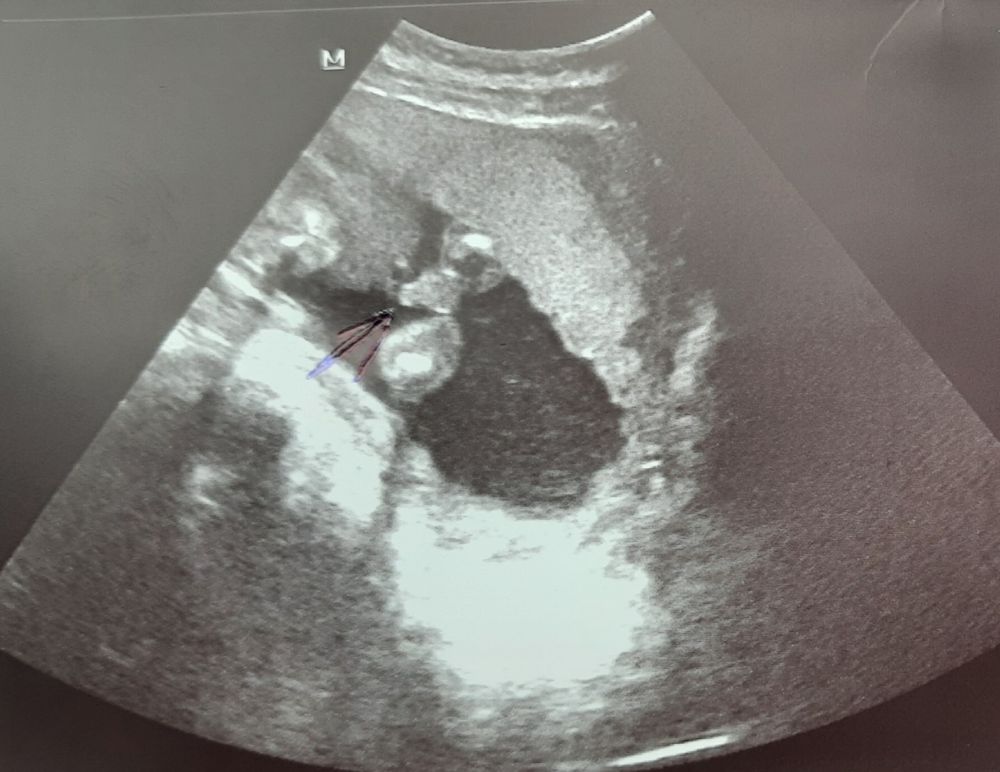

УЗИ 16 недель

В 16 недель уже между ног смотрят, тут такого обзора нет

Это профиль ребёнка. Пол - между ножек 😊

Между ножек должно быть фото)У нас вот, ножки и посередине ручкой отмечена мошонка) мальчик) у девочки по идее полосочка между ножек) а в профиль не особо увидишь)

Юлия, у нас только в профиль фото) ну ладно раз сказали девочка, значит ждём девочку 🥰

Ольга, наверное врач посмотрела, увидела всё, сказала, а фото сделала красивое, для вас😊 В 16 недель редко ошибаются, не переживайте)